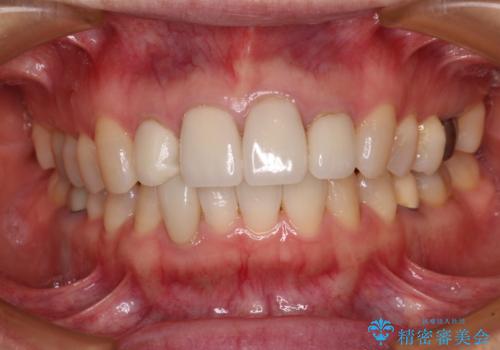

- 上顎4前歯に装着されているセラミッククラウンのうち、ひとつが欠けてしまったとのことで来院された患者様です。

土台となっている歯には問題がないため、周囲のセラミッククラウンと色調が合うように、オーダーメイドタイプのセラミッククラウンにて補綴治療を行うこととしました.

欠けてしまったセラミッククラウンはガラス系セラミッククラウンであったため、今回製作する歯は、強度の強いジルコニアセラミッククラウンとしました。

クラウンの種類は異なりますが、色調の適合したクラウンを装着することができました。